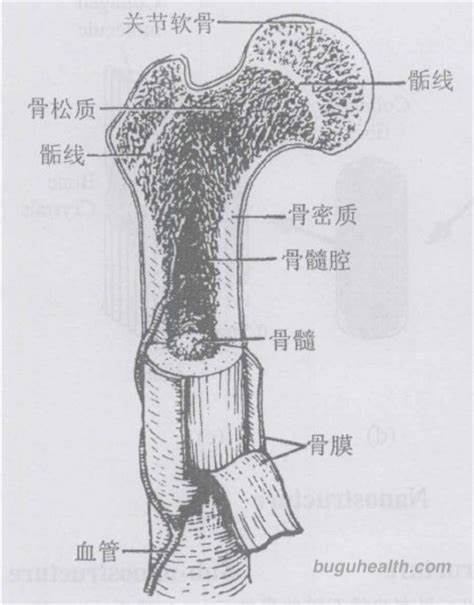

- ÿ��������206��ǣ�����λ�ɷ�Ϊ�ǡ����ɹǺ���֫�������֣�����ǰ����ͳ��Ϊ����ǡ�������̬��ͬ��һ��ɷ�Ϊ���ǡ��̹ǡ���ǺͲ���������֡�����ϵͳ��ά�������������ܵ���Ҫ��ɲ��֣���ά�����Ρ�֧�����غͱ����ڲ����١��ǵ���̬��������������ϰ�ߡ��Ͷ����ʼ��Ƿ���ijЩ����������һ���ı䡣�ڶ�ͯ����.....